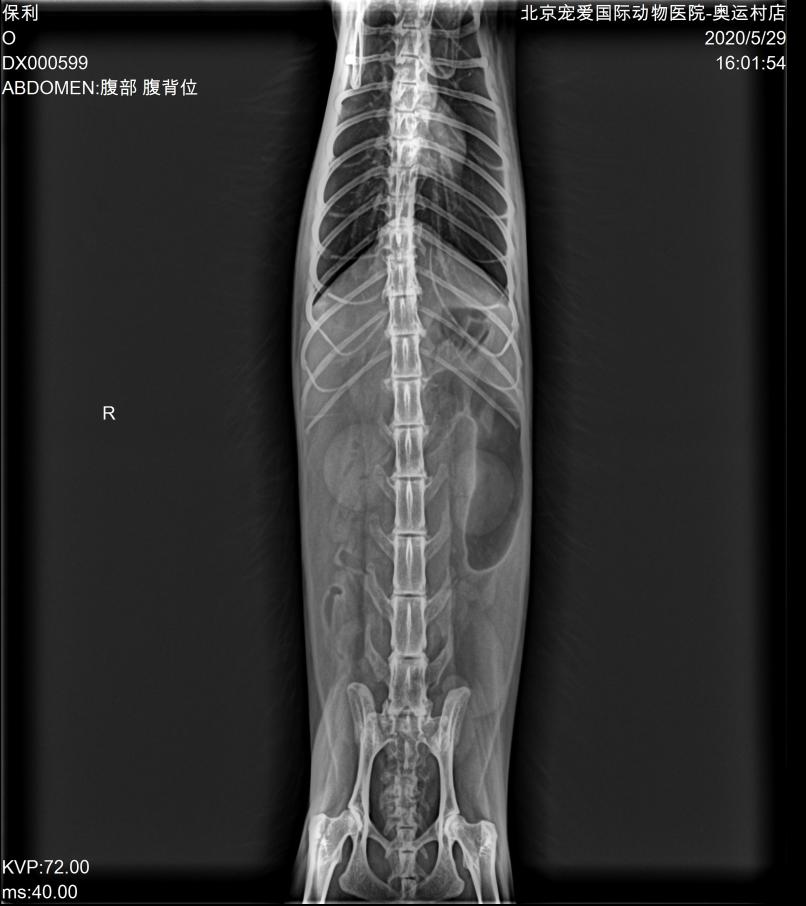

DR:

DR显示胃肠道空虚,未见阳性异物。

腹部彩超:

超声显示双肾萎缩,皮髓质分界减弱,提示慢性肾病;肝脏整体回声增强,提示肝脏脂质沉积;胆泥淤积,胆管堵塞。